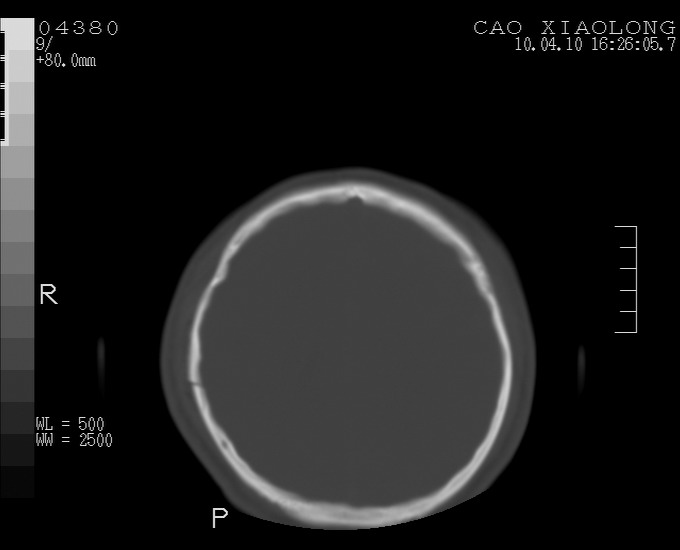

以下是引用随光逐影在2010-4-11 11:00:00的发言:[br]1)左侧额颞顶部硬膜下血肿。2)蛛网膜下腔出血。3)右侧颞顶部颅骨线形骨折。[br][br]20小时后复查:左侧额颞叶脑挫裂伤;左侧额颞顶部硬膜下血肿及蛛网膜下腔出血有吸收表现;右侧颞顶部颅骨线形骨折。[br]